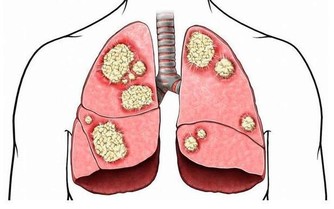

此外,2016年的腫瘤年鑑研究發現,患有牙周炎的男性整體患癌症的可能性高13%,

而患有嚴重牙周病的男性患癌的可能性高出45%。

那些與吸煙相關的癌症,如肺癌、膀胱癌、食管癌、腎癌、胃癌和肝癌似乎最受影響。